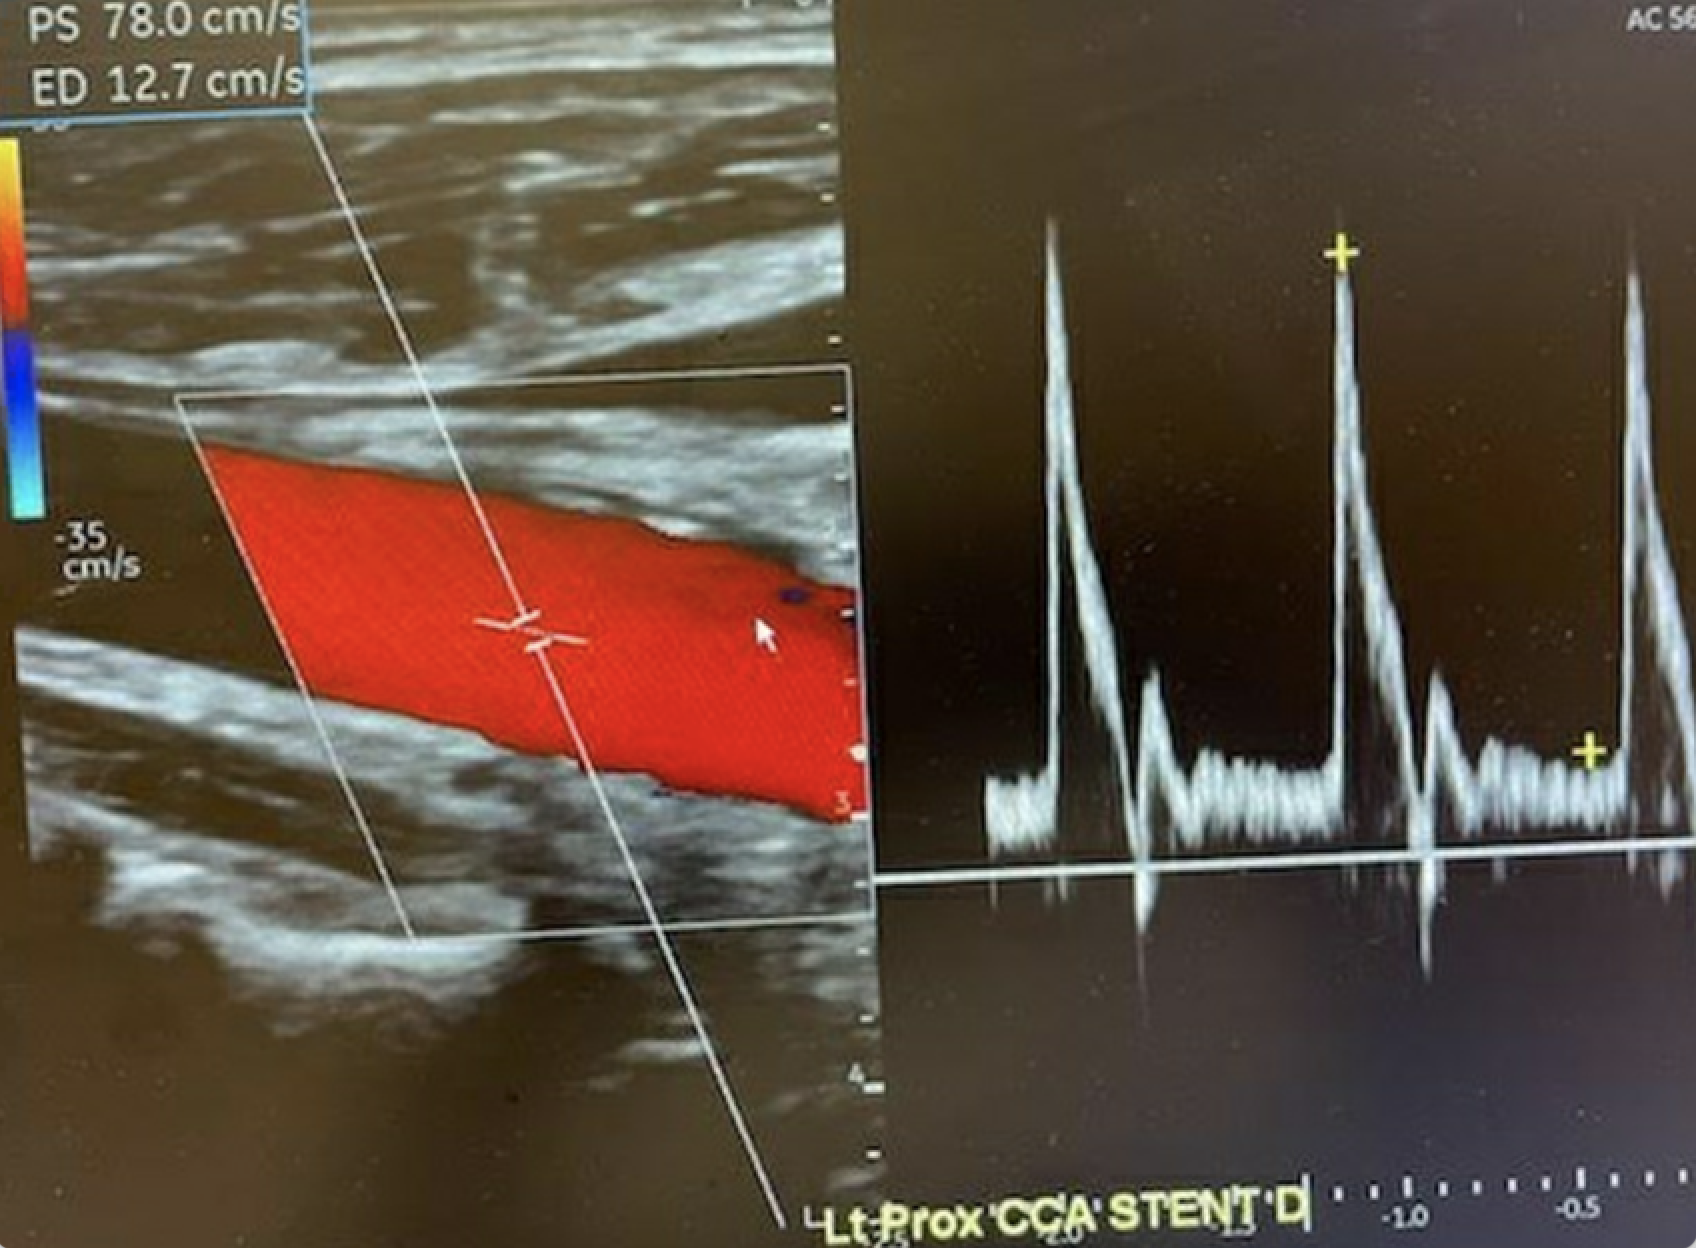

The patient’s neurological status improved with a normal LOC and improvement in the left-sided weakness. A week later he only had mild left arm weakness. He then underwent retrograde stenting of the dissection involving the mid right CCA utilizing a 12-mm x 100-mm Abre self-expanding venous stent with complete restoration of the lumen of the right CCA.

Over the next few days, the residual left arm weakness completely resolved. On 30-day follow-up, he was noted to have an essentially normal neurologic examination with normal motor function of the left upper extremity (Figure 5). At 1 year, the patient remained free of neuro deficits.